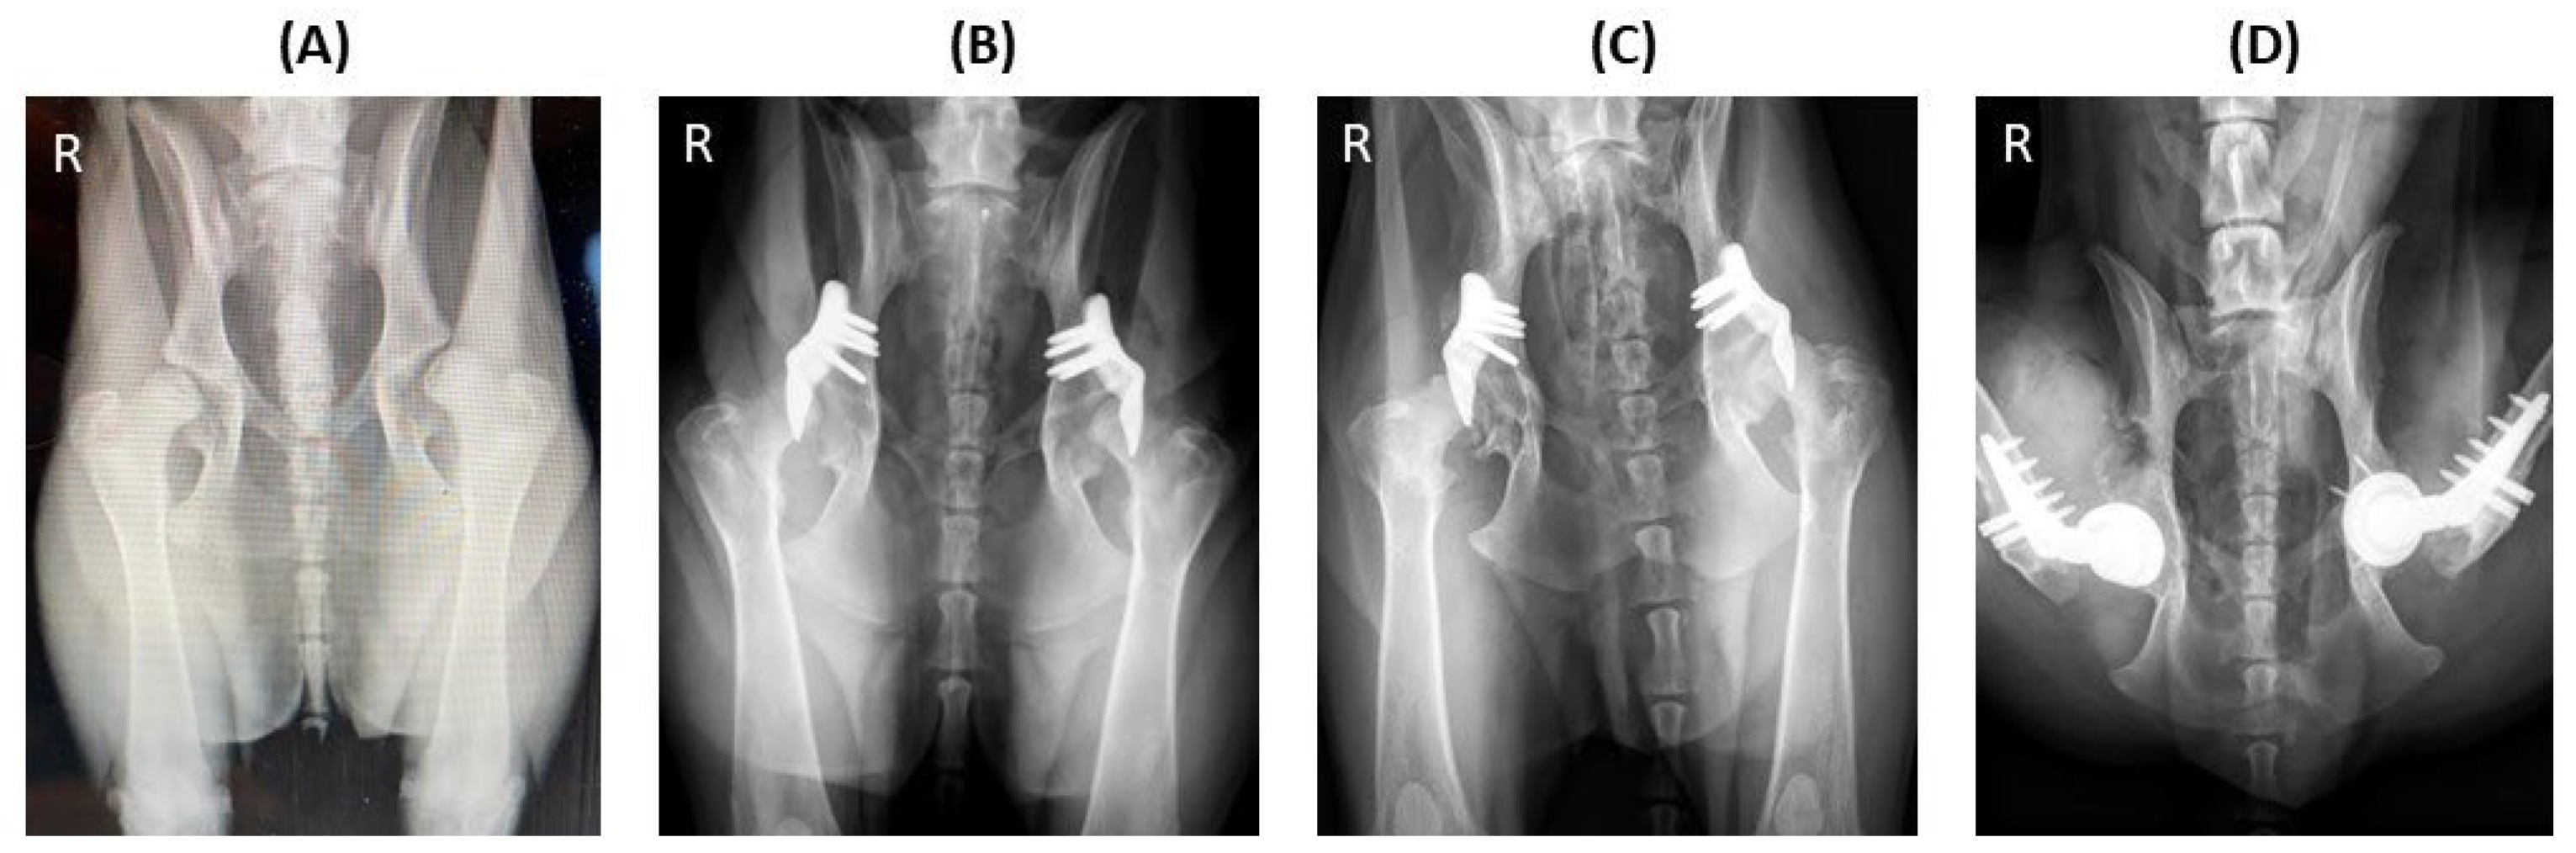

3.2. Radiographic Outcomes

NA (◦) | 88.5 12.6 a | 137.6 19.2 b | - | 134.3 19.0 b | 131.5 17.8 b | < 0.000 |

| LFO (%) | 24.3 16.2 a | 83.8 16.4 b | - | 79.8 18.2 b | 78.1 17.4 b | < 0.001 | |

| PC (%) | 34.7 17.3 a | 82.3 20.0 b | - | 80.2 18.8 b | 77.4 19.5 b | < 0.001 | |